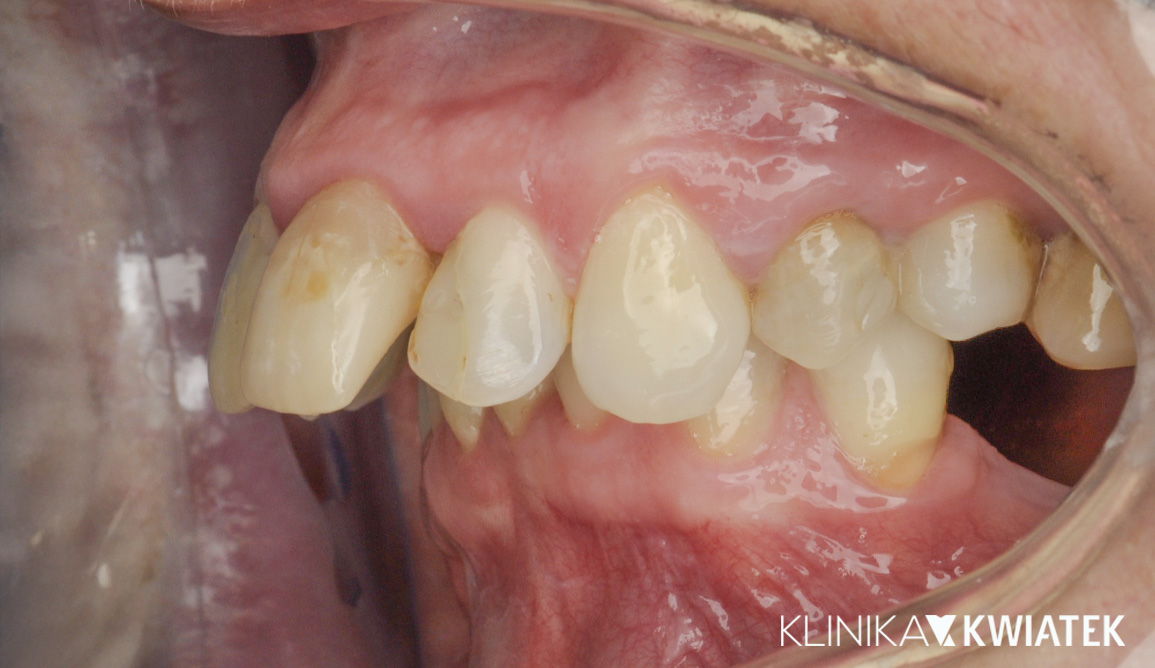

Jak uśmiech pokonał strach – metamorfoza pełna zaufania

Pacjent przez wiele lat unikał wizyt u dentysty z powodu silnego lęku. Strach przed leczeniem sprawił, że w jamie ustnej pojawiły się rozległe zmiany próchnicowe i liczne zęby wymagały ekstrakcji.

Po dokładnej diagnostyce i rozmowie, wiedząc, że Pacjent wyklucza leczenie ortodontyczne, krok po kroku wdrożono kompleksowy plan leczenia – od higienizacji i leczenia zachowawczego, przez zabiegi chirurgiczne i endodontyczne, aż po odbudowę braków zębowych na implantach.

Dziś Pacjent z dumą i spokojem uśmiecha się bez lęku – cieszy się zdrowym, estetycznym uśmiechem, stabilnym zgryzem i doskonałą higieną jamy ustnej.